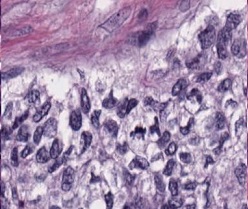

However, nuclei and glands instance segmentation cannot be regarded as a simple task for non experts in pathology labs. Despite being continuous advancements in learning algorithm, nuclei segmentation is still an extremely challenging task because of blurred nuclei boundaries, differences in size and shape highlighted by Vahadane et al. [12], uneven staining, pathological changes on pathological images, morphological abnormalities [13] and substantial color variations described by Rashmi et al. [14]. Similarly, varying morphology of glands at different histological grades, different intrinsic features of glands WSIs poses major challenge during segmentation of instances. Firstly, applying mathematical shape model for instance segmentation gets difficult due to shapes heterogeneity. Figure 2 shows structural variations of nuclei in different organs. Secondly granule filled cytoplasm cause nucleus extrusion to flat shapes as compared to oval or round structures in normal cases mentioned by Yan et al. [15]. Thirdly, cellular matrix variations results in anisochromasia thus resulting in additive noise in background compared to normal intensity gradients.

Improper staining often times result in similarity in nuclei to cytoplasm or background colors thus yielding blurred boundaries [16]. Moreover occurrence of several overlapping nuclei in whole slide images causes further difficulty in objects segmentation. Major challenge in model development is varying types of nuclei e.g nerve cell nuclei are typically triangular in shape [17], while glial and oligodendrocytes nucleus are usually round in appearance but the later one have light rings as, astrocytes have oval shape, endothelial cells are usually slender in structure [18], while malignant tumor cells have irregularly shaped nuclei [19]. Developed model is supposed to be robust enough to detect all these kinds of nuclei without any mislabelling. Digital image quality variation, background clutter, image artifacts are some other extremely important yet least discussed problem in this domain. Nuclei curvature variation also impacts detection since normally in pathology images, nuclei contour points curvature changes smoothly [20]. However, given a single contour having two or more touching or occluding nuclei, results large curvature change at touching points. Already existing automated medical image analysis tool use classical segmentation including active contour models, watershed or thresholding techniques for nuclei instances identification. These tools needs configuration with respect to each data to accurately analyze distinct microscopic modalities including scales and experimental variation, thus leading to an evident requirement of technological domain expertise for accurate algorithm selection and parameters adjustment. Still for proficient ones too, this choice can be daunting, considering that every year numerous papers are published, presenting new research techniques for gland and nucleus instance segmentation. Even after examining under controlled experimental conditions, no single technique can be generalized for segmenting all microscopy images correctly, since classical machine learning algorithms are either sensitive to technical artefacts or often fails in adapting to biological samples heterogeneity. Altogether, this situation yields slows pace of research and at times inhibits research laboratories from adopting newer image analysis technologies owing to the time and expertise required.